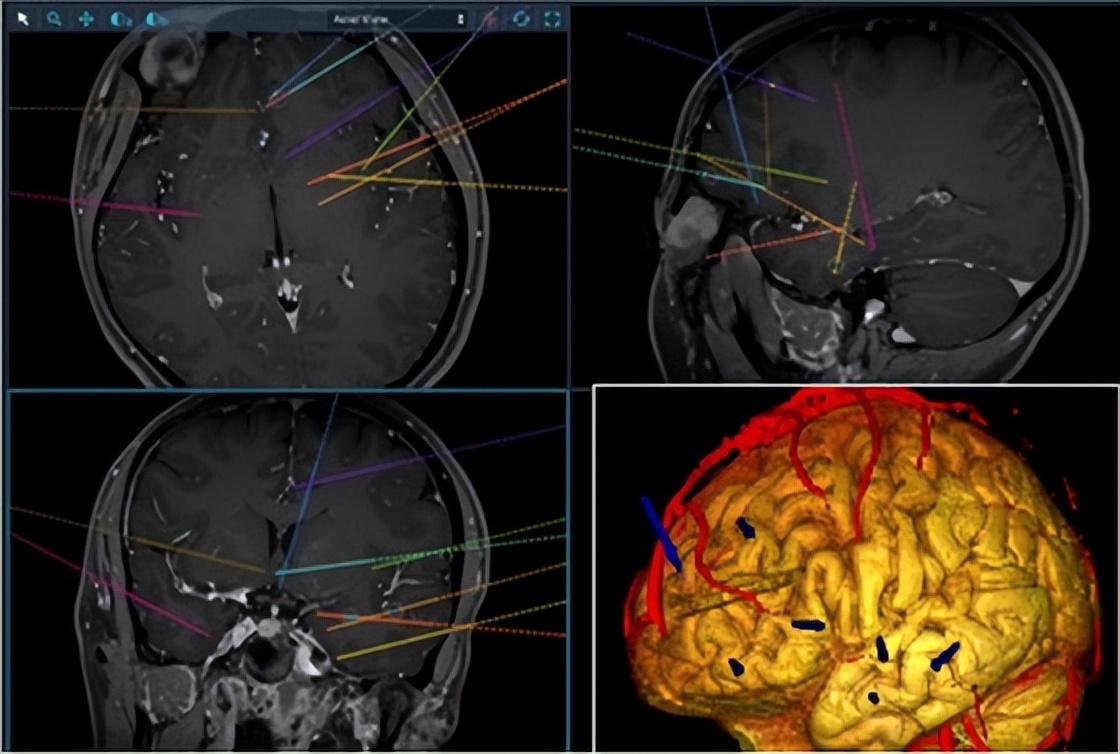

上海市东方医院作为三甲公立医院,其功能神经科熟练运用SEEG、颅内电极等先进外科评估技术,熟练运用病灶切除根治术、迷走神经电刺激术、立体定向神经核团调控术等外科及微创神经调控手术技术,通过神经内科、神经外科、影像科、神经电生理等多个学科的共同合作,制定药物治疗、手术治疗和术后评估方案,为难治性癫痫患者提供最适合的诊疗个体的治疗。

SEEG微创手术技术 让频繁癫痫消失不见